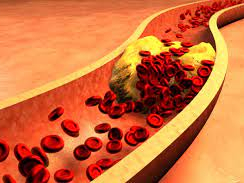

고지혈증은 혈중에 지질 성분이 증가한 상태에서 필요 이상의 지방이 혈액 내에 존재하며

혈관벽에 지방이 쌓여 염증이나 심혈관계 질병 등 다양한 질환을 유발하고 있는 상태입니다.

●고혈압&고지혈증 방치하면?고혈압을 방치하면 인체기관의 손상이나 관상동맥 또는 뇌혈관 등에 죽상경화를 유발하여 심부전, 협심증, 뇌졸중, 뇌출혈, 심근경색, 시력저하 등 다양한 합병증이 발생할 수 있습니다.

또한 고지혈증으로 인해 혈중 중성지방 수치가 높을 경우 췌장염, 황색종, 죽상경화증, 협심증, 뇌졸중, 심근경색 등의 질병을 유발할 수 있습니다.